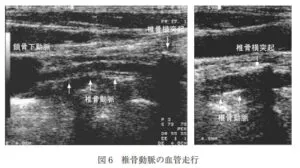

椎骨動脈の描出は総頚動脈を描出し、プローベを頸部の外側に移動すると椎骨の横突起がアコースティックシャドーとして描出されるので、横突起間にある血管を探す。本血管が見える場合には、浅いほうが椎骨静脈、深いほうが椎骨動脈である。両者の鑑別は血流波形で確認しておく必要がある。椎骨動脈を心臓側に追ってゆくと鎖骨下動脈の起始部まで観察することも可能である。